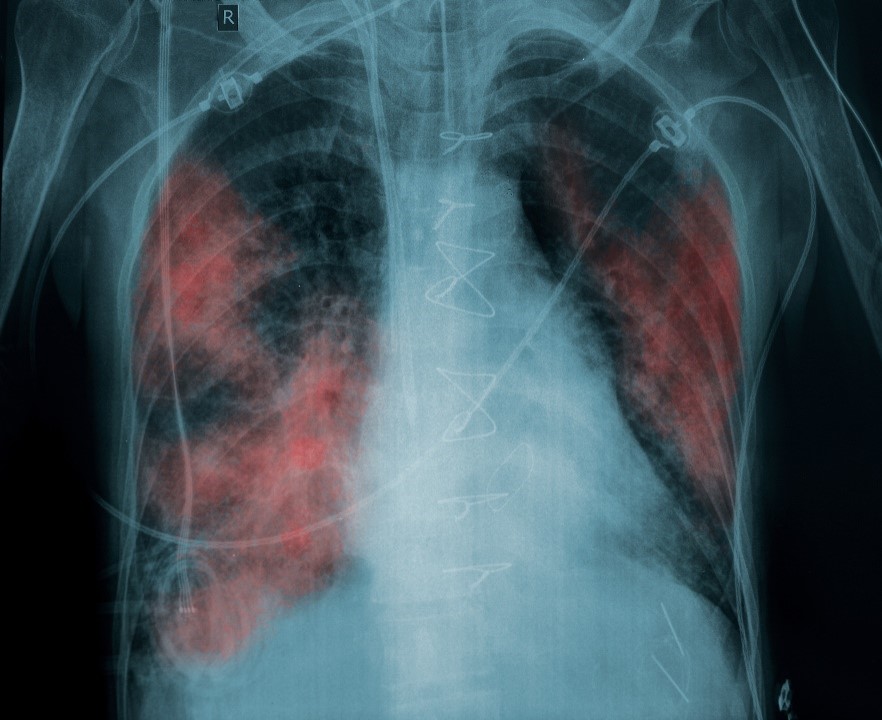

Crystalline silica artificial stone—also referred to as artificial stone, engineered stone or manufactured stone—is widely used in residential and commercial kitchen and bathroom countertops. Artificial stone contains at least 90% crystalline silica that is nano-sized and ultra-fine in size, and the remaining portion is made up of toxic metals, and resins that produce volatile organic compounds (VOCs). When crystalline silica artificial stone slabs are fabricated (cut, ground, or polished), it releases nano-sized crystalline silica and other toxic particles into the air. Breathing this dust causes artificial stone accelerated silicosis, a progressive and fatal lung disease.

As artificial stone silicosis advances, inflammation and scarring in the lungs becomes more severe. This may lead to:

- Pulmonary fibrosis